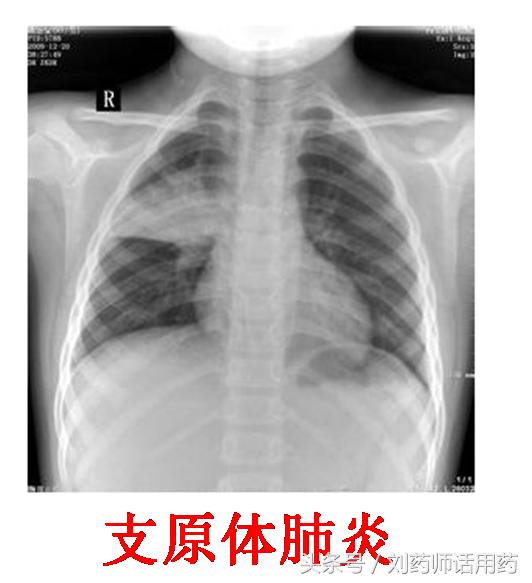

据统计,儿童肺炎支原体肺炎占到儿童社区获得性肺炎的10%一40%。虽然四环素类、氟喹诺酮类仍然保持着对肺炎支原体的强大抑菌活性与临床疗效。但四环素类因可能使牙齿发黄或牙釉质发育不良等不良反应,故仅应用于8岁以上患儿。而喹诺酮类可能对骨骼发育产生不良影响,18岁以下儿童使用受到限制。